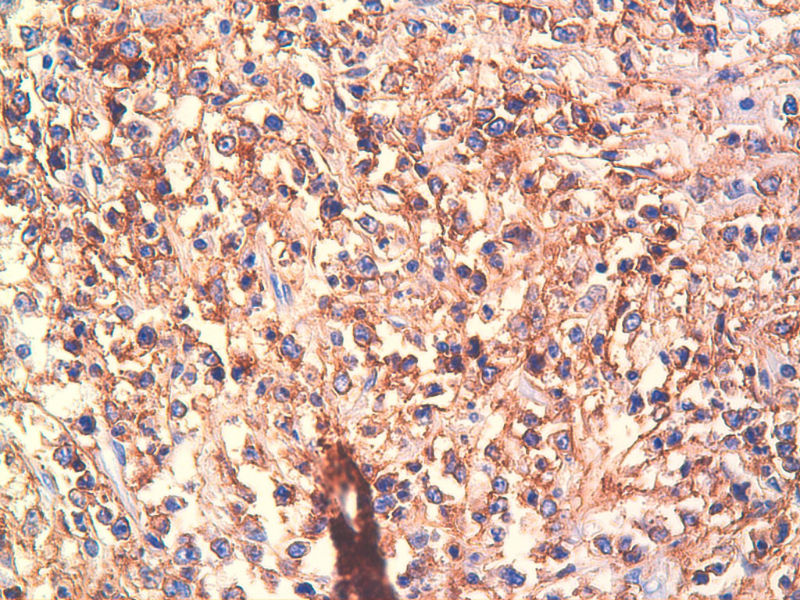

免疫组化染色:CA125(-),PLAP(-),NSE灶状阳性,Vimentin(+),a-inhibin(-),CK7(-),CK20(-),CD15(-),PSA(-),S100(-),MyoD1(-),CD38(-),CD56(-),HMB45(-),CK8(-),NF(-),CGA(-),syn(+),MPO散在(+)可能是炎细胞吧,LCA(+),CD133(+).

是的,syn(+),LCA(+), CD79a阳性, CD3阴性,NSE是局部胞核,胞浆着色,主要是胞浆着色;SYN也是局部,主要是胞核着色,胞浆很少。不对吗?我也迷糊。也许我看错了,不像那种典型的胞浆颗粒状着色。大家帮看一看。

今天又做了免疫组化,请大家帮看看。CD10(-),CD138(-),CDX2(-),CD3(-),CyclinD1(-),CD2(-),CD117(-),CD7(-),CD30(-),CD23(-);CD20强(+),BCL-2,Bcl-6,EMA,PAX-5,MUM-1,CD5,ALK,CD68都是散在阳性,大家帮确定一下是否阳性。B细胞淋巴瘤可以确定了,不知是哪种类型的?